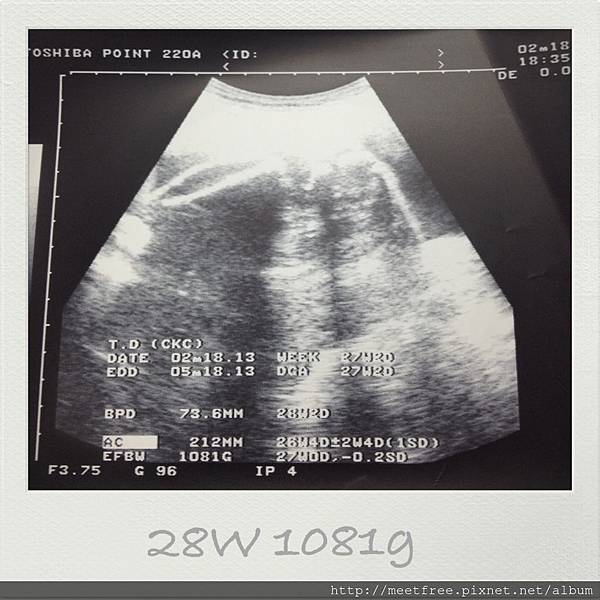

• 【媽咪日記】-時間~咻一下,到了28W囉!!

28w2013/02/18 Mon.(一)

年後開工第一天,也是晚上要跟小妞約會的時刻,

不知道小妞是知道晚上要跟爸比&媽咪相見歡,從早上就開始好動個不停,

連等紅綠燈也是扭來扭去不停歇,